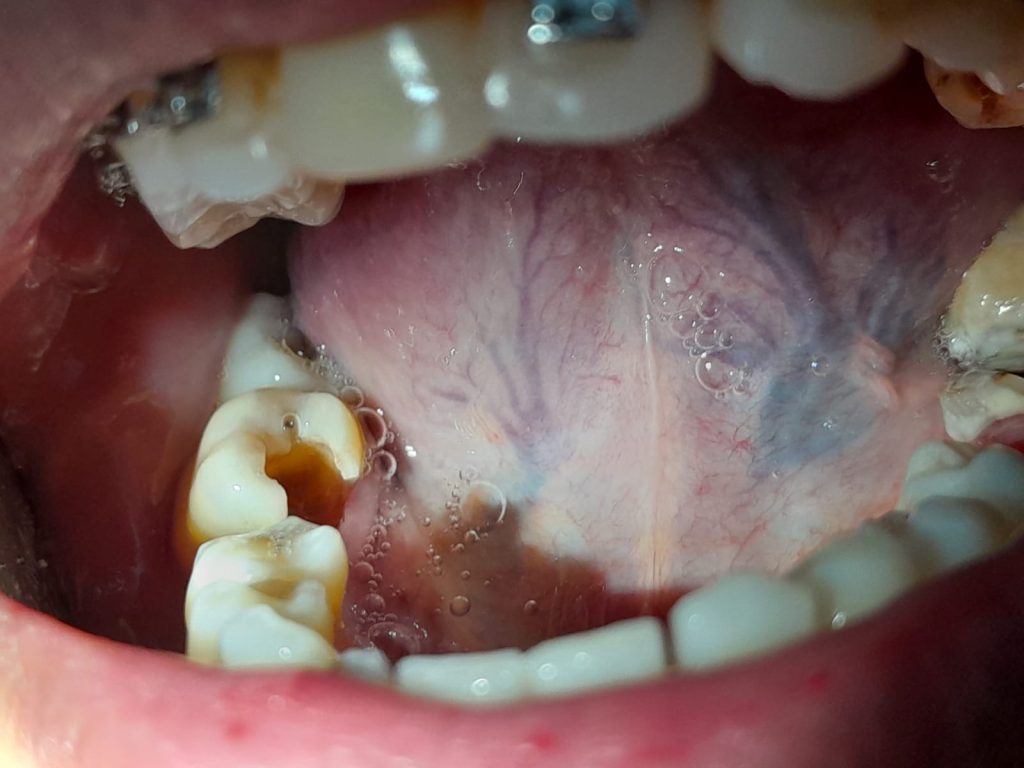

Gigi berlubang adalah lapisan terluar gigi yang rusak karena terkikis lapisannya. Gigi berlubang umumnya diawali oleh munculnya plak di permukaan gigi. Pembentukan plak gigi seperti lapisan yang lengket pada gigi. Kondisi ini terjadi karena terlalu sering mengkonsumsi makanan manis dan tidak membersihkan gigi dengan baik. Bila sisa makanan manis tidak dibersihkan dari gigi maka bakteri bakteri akan dengan cepat bertumbuh dan membentuk plak. Kombinasi antara bakteri, asam, sisa makanan yang ada di mulut, dan air liur, akan membentuk plak yang melekat pada gigi.

Asam yang terdapat dalam plak secara perlahan mengikis lapisan gigi, hingga membuat gigi menjadi berlubang. Pembentukan asam pada plak dapat menghilangkan mineral pada email gigi dan bagian luar gigi. Erosi ini menyebabkan lubang kecil di enamel. Lapisan dentin lebih lembut dari enamel dan kurang tahan terhadap asam. Dentin memiliki tabung mungil yang secara langsung berkomunikasi dengan saraf yang menyebabkan sensitifitas gigi. Terjadinya pengeroposan Kerusakan gigi berlanjut hingga ke bagian dalam gigi yang dinamakan pulp . Pulp menjadi bengkak dan teriritasi oleh bakteri. Terjadinya pembengkakan yang menekan saraf dan gigi merasakan sakit.